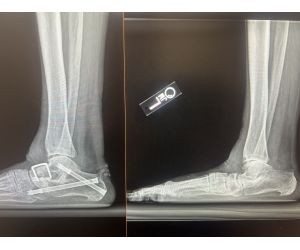

Failed Total Ankle Arthroplasty - What Would You Do?

Naji S. Madi, MD

How are you managing failed total ankle replacement? This patient underwent an ankle replacement 5 years ago at an outside hospital. Patient has...